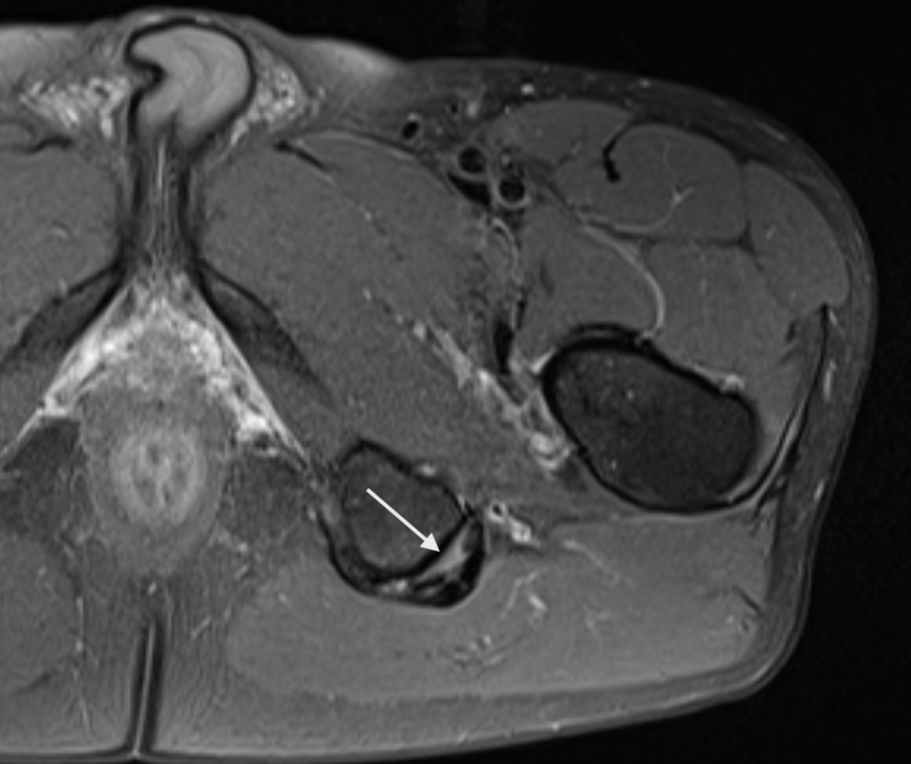

Consent✅ 1 year progressive severe (painless) L calf atrophy & weakness Medial bulk affected > lateral - see pic Affecting football performance Rolling over in bed onto R side - sudden 'spasms' in leg leg US - diffuse fatty atrophy of medial gastroc & soleus (vs R) EMG / NCS - severe L5 & S1 subacute chronic radiculopathy MRI - no herniated disc - but 5cm filum terminale lipoma (high signal on T1 seq, low on STIR). Also very low lying conus medullaris & tethered cord suggestive of spinal dysraphism (spina bifida occulta) Neurosurgical referral